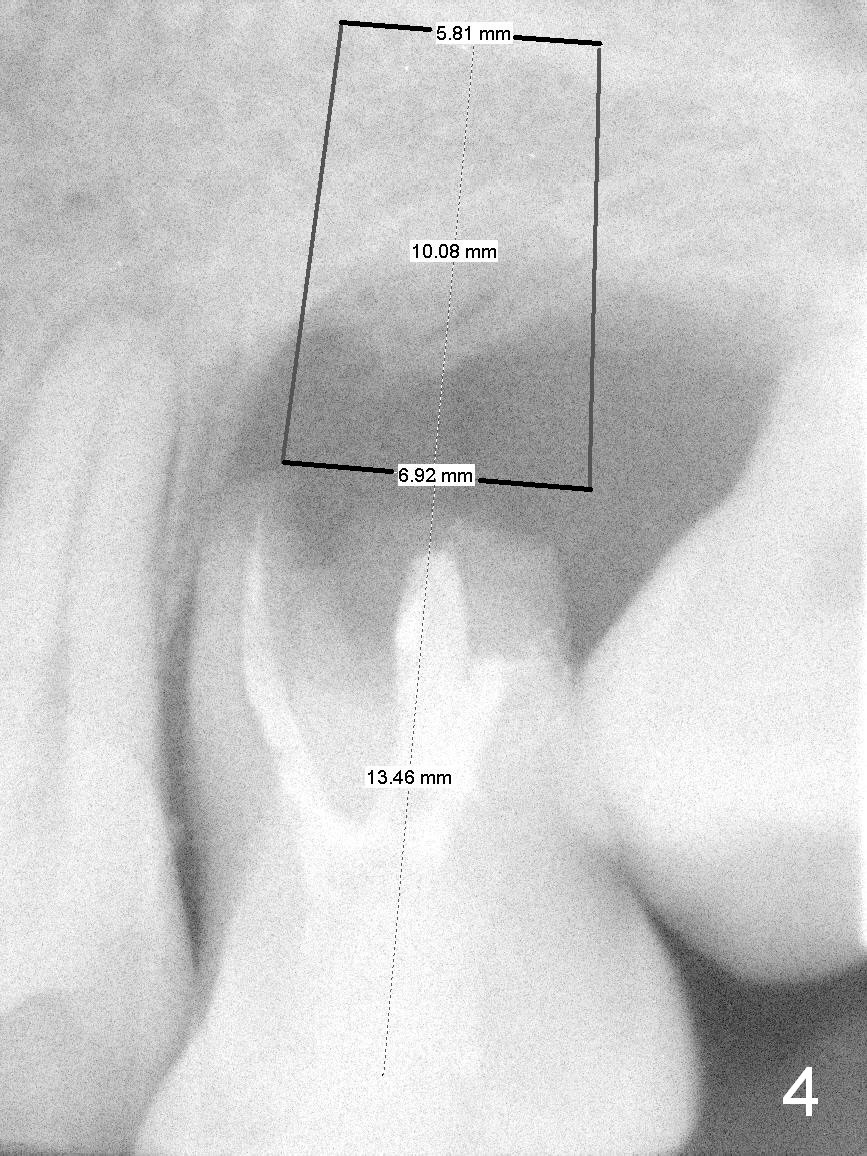

A 42-year-old man (XK) has perio-endo disease at the tooth #14.  After root canal therapy (Fig.1), the tooth remains nonsalvageable.  The bone loss is extensive (Fig.1 *) and uneven (more bone mesially than distally) after extraction (2% Xylocaine/1:50,000 Epinephrine).  A bone-level implant is placed in an ideal depth (Fig.3 UF; Fig.4 SM), irrelevant of the gingival margin, first.   Place bone graft distally (Fig.3 red circles) before choosing a proper abutment.  For example, there is plenty of combination to choose cuff and abutment lengths for a SM or UF implant (Fig.4).